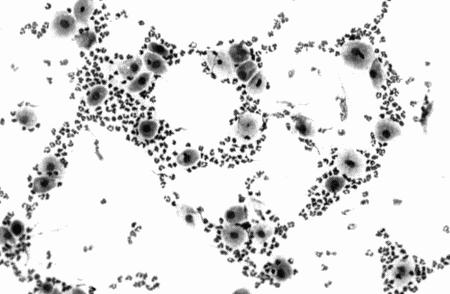

Фиг. 4.1.

Цитология вагинальных выделении при расщепленной течке; на б день после начала проэструса. Вмазке преобладают промежуточные и ядерные поверхностные клетки (см. Приложение)